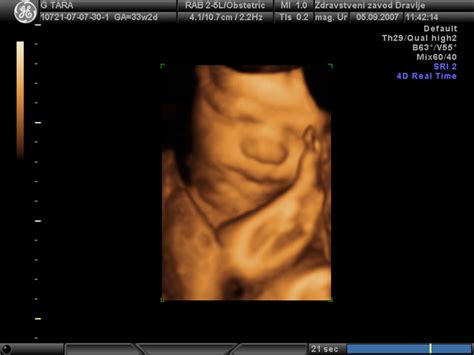

- 27. in 28. teden: Plod doseže težo 1000 g in dolžino 35-40 cm.